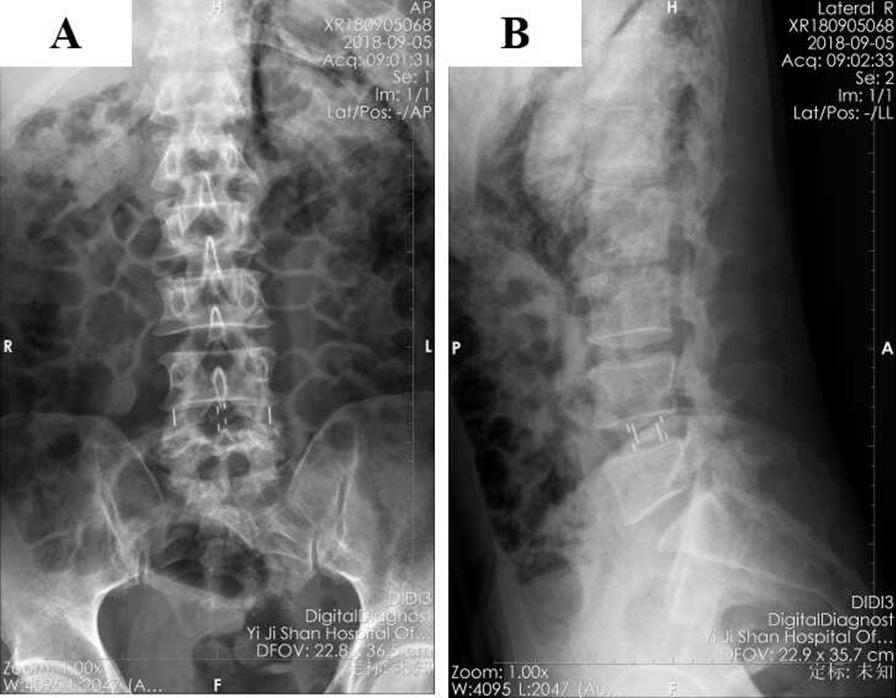

A 55-year-old male patient of Han nationality was diagnosed with lumbar spinal stenosis and underwent standalone oblique lateral interbody fusion surgery under general anethesia. Three days after the operation, subcutaneous gas accumulation appeared in the left lower abdomen of the patient with no inflammatory reaction of the wound. He was treated with conservative management, and the retroperitoneal pneumatosis and subcutaneous emphysema had disappeared completely 1 month later.

一名 55 岁汉族男性患者被诊断为腰椎管狭窄症,并在全身麻醉下接受了单纯斜外侧椎间融合术。术后 3 天,患者左下腹部出现皮下积气,伤口无炎症反应。他接受了保守治疗,1 个月后腹膜积气和皮下气肿完全消失。